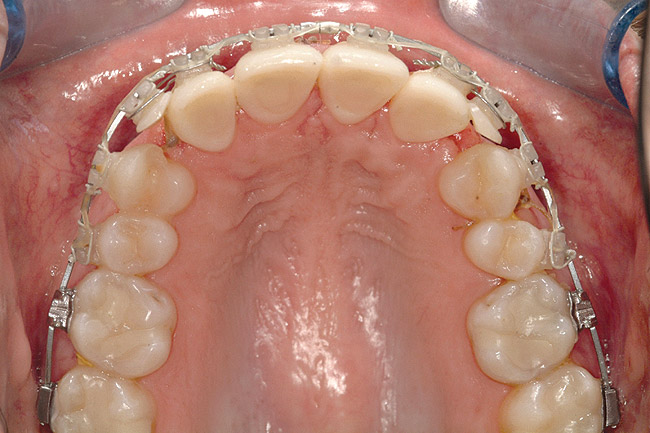

Fig 6 (and Fig 7). Prerestorative orthodontics was completed in 5 months. Final result 3 years, 4 months after completion.

Figure 6

Fig 7 (and Fig 6). Prerestorative orthodontics was completed in 5 months. Final result 3 years, 4 months after completion.

Figure 7

Fig 8 (and Fig 9). Teeth Nos. 5 and 12 were converted to Nos. 6 and 11, and Nos. 6 and 11 were converted to Nos. 7 and 10. Nos. 4 and 13 were enlarged. Note stability and absence of orthodontic relapse. Before-and-after smiles. Periodontist: Edward P. Allen, DDS, PhD. Prosthodontist: Robert R. Winter, DDS.

Fig 9 (and Fig 8). Teeth Nos. 5 and 12 were converted to Nos. 6 and 11, and Nos. 6 and 11 were converted to Nos. 7 and 10. Nos. 4 and 13 were enlarged. Note stability and absence of orthodontic relapse. Before-and-after smiles. Periodontist: Edward P. Allen, DDS, PhD. Prosthodontist: Robert R. Winter, DDS.